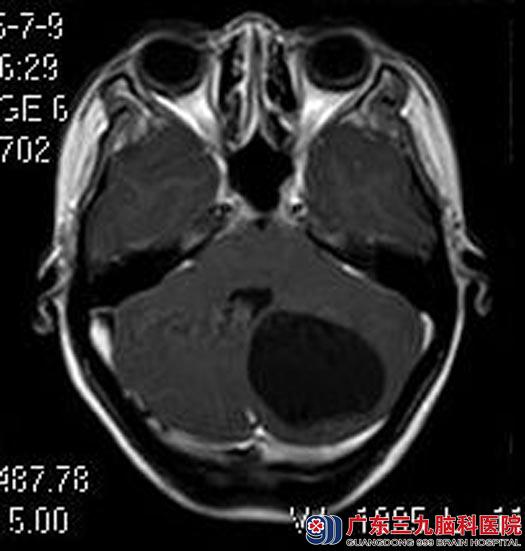

徐小姐担心有误诊,急忙找到广东三九脑医院综合神经外科的鲁明主任。进一步头颅MR检查提示:左侧小脑半球囊实性占位性病变,大小约4.9cm×3.2cm×4.2cm。

▲手术前